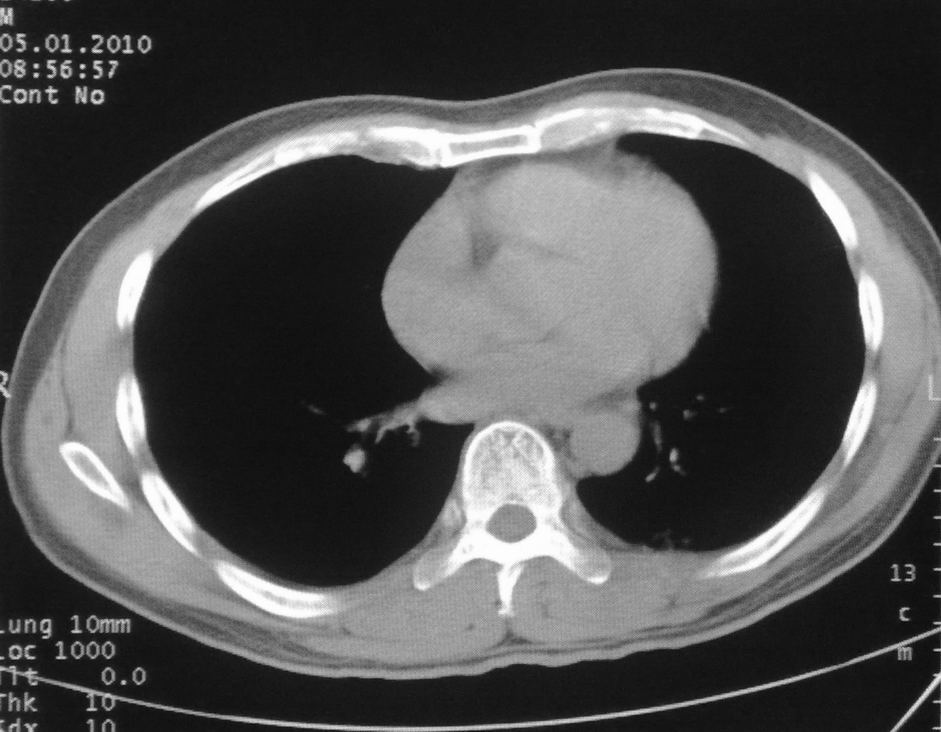

男,51岁,左胸前区不适数天。

薄壁空洞,边缘毛刺,胸膜凹陷,考虑肺癌,结核不排除。

考虑左肺下叶感染性病变。

考虑左肺下叶感染性病变,不除外肺栓。